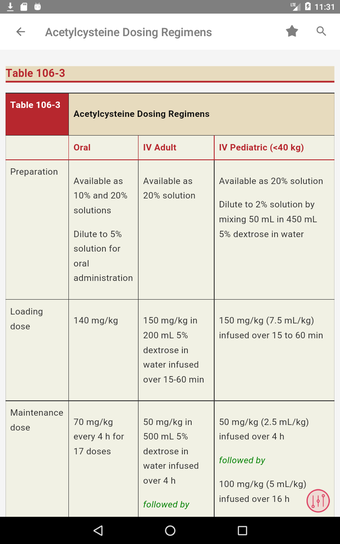

この無料アプリには、日常の実践に役立つ多くの情報が含まれています。このアプリでカバーされるトピックは、疾患から薬剤、さまざまなタイプの傷害まで幅広く、患者ケアを担当する人々にとって素晴らしいリソースです。